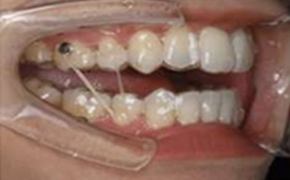

マウスピース矯正後

マウスピース矯正終了後に行う仕上げの矯正です。

仕上げで「微調整したい」ときなどに行います。マウスピースとゴムを利用した方法や、短期間だけ最小限にワイヤーを使用する方法があります。